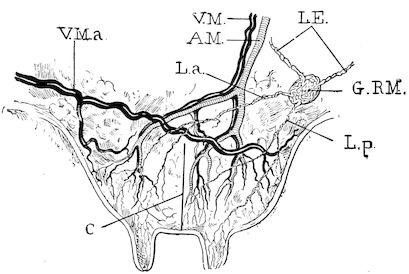

| Castration of the cow | 761 | |||

| Castration of the sow | 765 | |||